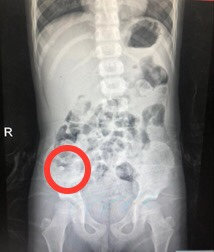

阳阳的父母迅速将他送至附近医院。为准确判断牙齿的位置,医生们首先为他进行了CT检查。CT扫描是一种先进的医学影像技术,它如同透视眼一般,能够提供关于身体内部结构的详细信息,帮助医生准确定位问题并作出相应的处理。通过CT扫描,医生发现那颗牙齿正卡在阳阳的右主支气管中,情况十分危急。若不及时取出,随时可能引发呼吸困难,甚至更严重的后果。

图1 胸部CT显示右主支气管见一牙齿样异物